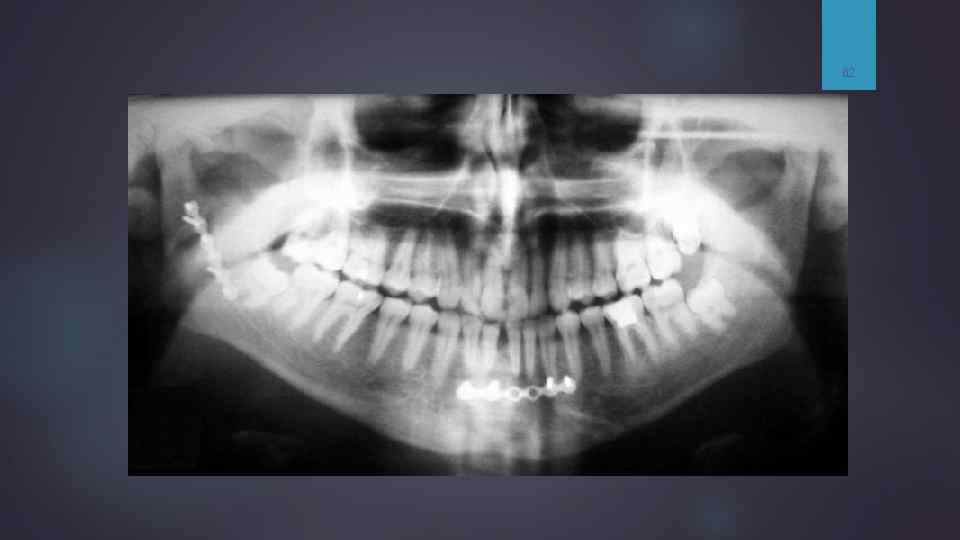

Перелом нижней челюсти 53 Зубы иммобилизированы проволокой (шинирование). На рентгенограмме черепа в носо-подбородочной проекции определяются нарушение целостности костной ткани нижней челюсти в области тела (подбородочного отверстия) слева с четкими неровными, мелко зазубренными контурами на уровне зуба 3. 2 шириной до 3 -4 мм, а также отмечается нарушение целостность стенки лунки 3. 2 зуба. Аналогичное нарушение целостности нижней челюсти отмечается справа в области угла нижней челюсти шириной до 4 мм в нижнем отделе и до 6 мм в верхнем, с нарушением целостности стенки лунки зуба 4. 7. В области нижнечелюстной вырезки справа отмечается нарушение костной структуры с формированием осколков в виде венечного и мыщелкого отросков. Заключение: шинирование. Множественные переломы нижней челюсти. Фиксация неудовлетворительная. Рекомендована МСКТ черепа для определения характера повреждения в области ВНЧС справа (расхождения отломков, наличия осколков).